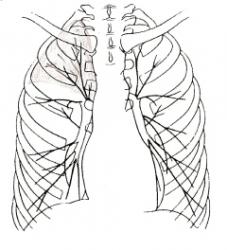

2 фаза развития рака, ведущим синдромом которой является гиповентиляция, в результате нарушения бронхиальной проходимости проявляется определенной теневой картиной.

1 степень сужения бронха – гиповентиляция характеризуется следующим:

- уменьшение прозрачности структурной единицы лёгкого (доли, сегмента) – иллюстрация 2, 3, 4;

- незначительное уменьшение объёма с намечающимися вогнутыми границами;

- сгущение сосудистого рисунка, что может создавать эффект «усиленного и обогащенного лёгочного рисунка в уменьшенных размерах доле, сегменте (иллюстрация 5. Заимствована из монографии «Рентгенодиагностика заболеваний органов дыхания». Авторы: Л.С. Розенштраух, Н.И. Рыбакова, М.Г. Виннер. М., «Медицина», 1987);

- расширение сосудов.